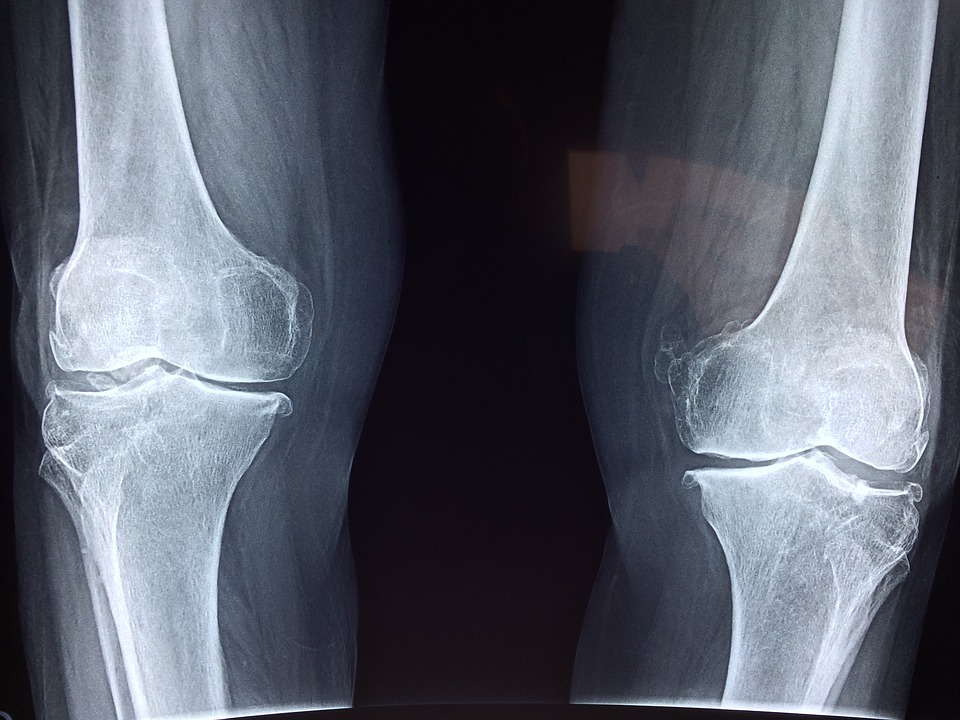

Des plaques et des vis sont généralement utilisées pour maintenir les »pièces » ensemble pendant que l’os guérit. Mais ce processus peut être long et douloureux. Une nouvelle merveille technologique pourrait rendre ces méthodes obsolètes. Ce nouvel outil potentiellement révolutionnaire est un implant en céramique imprimé en 3D, qui maintient ensemble les os fracturés tout en se transformant en os naturel.